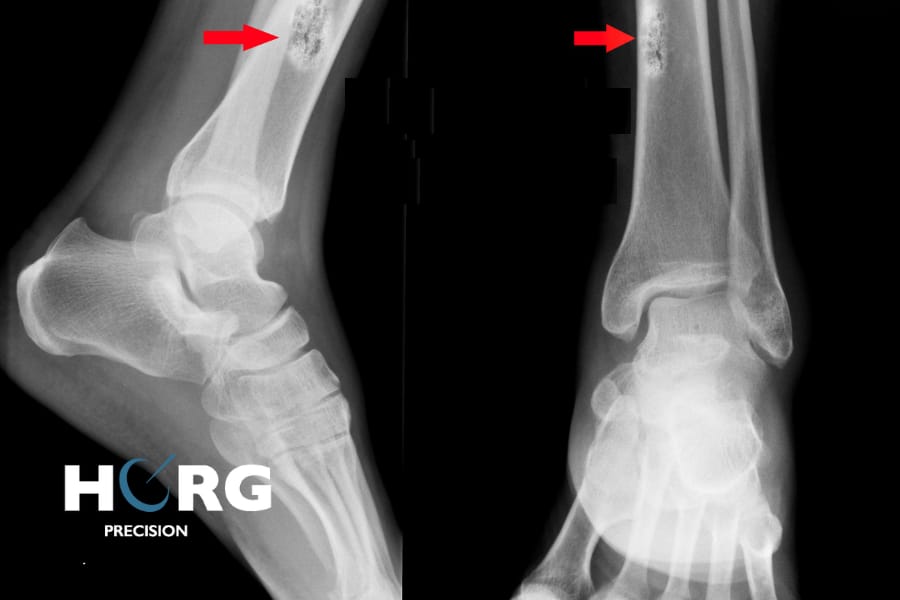

En cas de suspicion de cancer, différents examens d’imagerie médicale sont réalisés. Une radiographie permet de localiser une tumeur primitive osseuse, ou de rechercher des métastases – notamment pulmonaires.

Une IRM, un scanner et/ou une scintigraphie osseuse peuvent compléter la radiographie pour obtenir des images plus précises et réaliser un bilan d’extension.